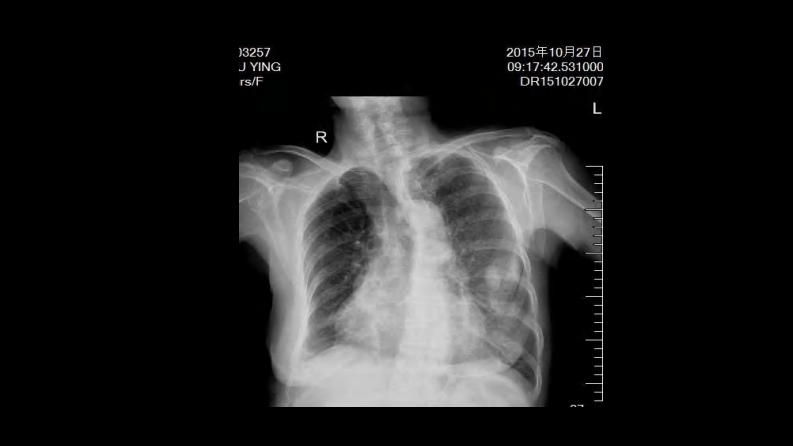

肺部空洞性病变CT与MRI.pdf